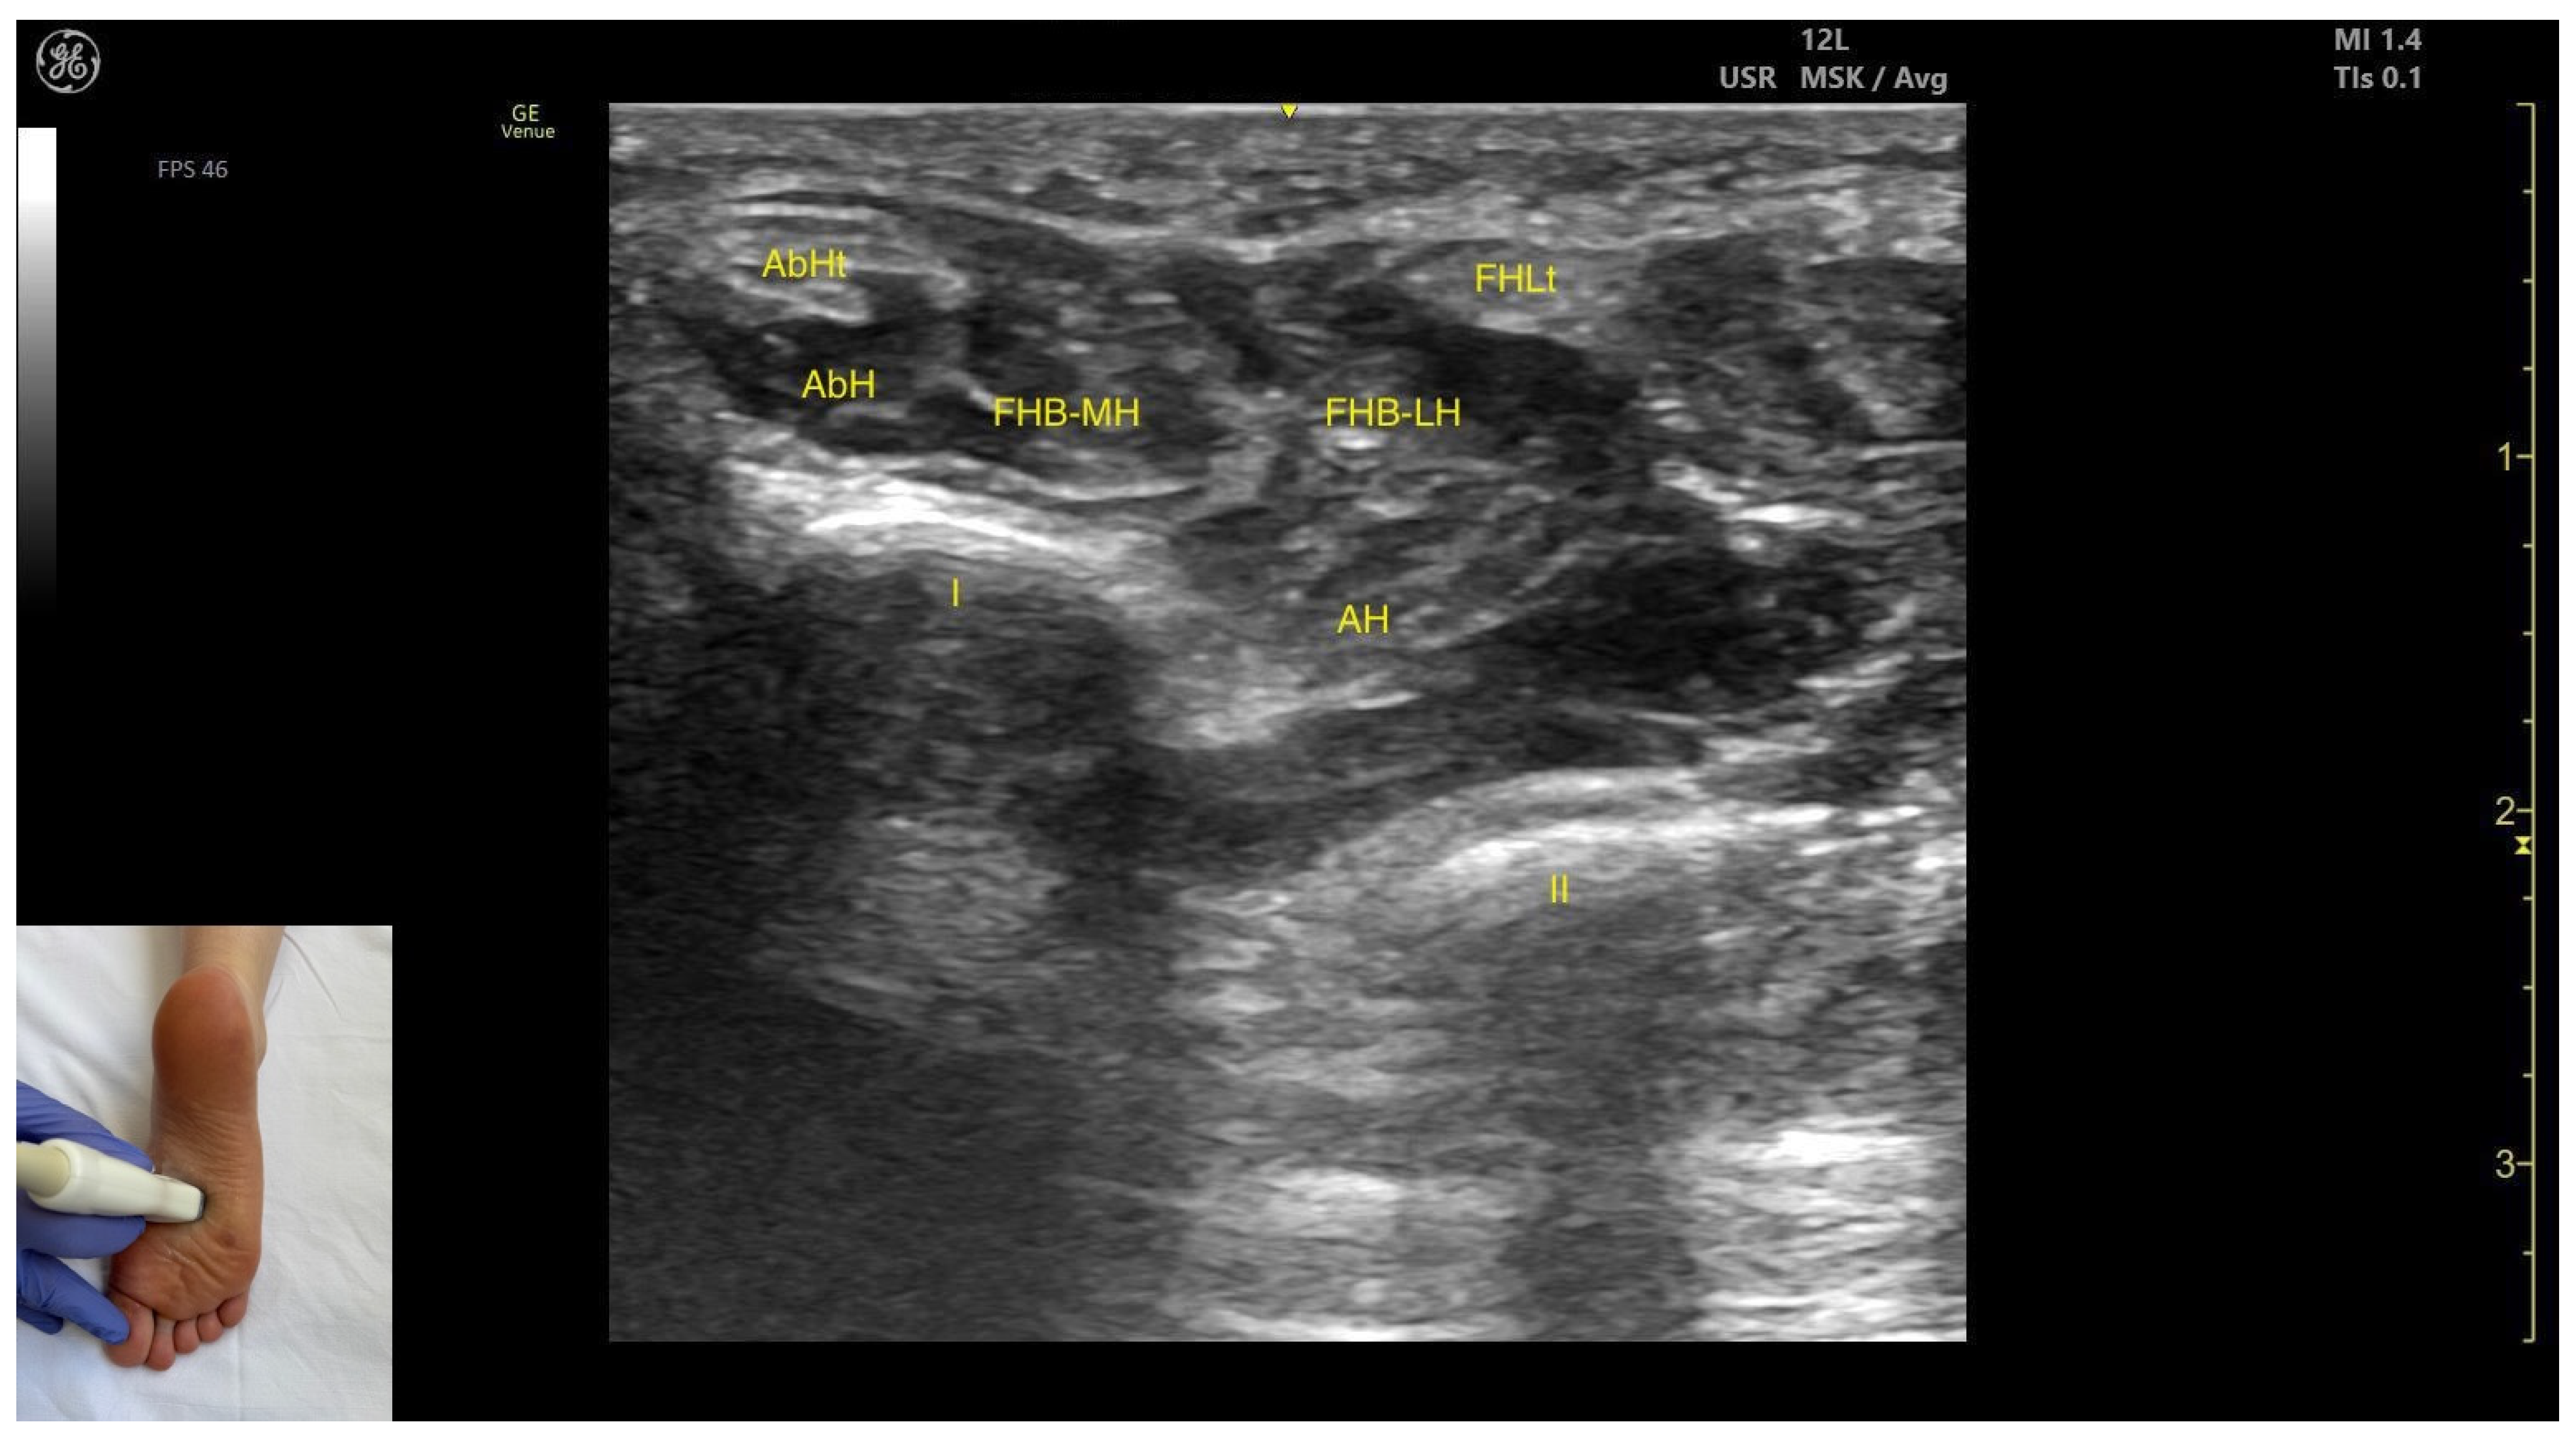

3.9.2. Ultrasound Identification

3.9.3. Key Ultrasound Landmarks

- Muscle position: It appears as a superficial muscle mass at this level. Medially, the abductor hallucis muscle and tendon are present; laterally, the tendon of the flexor hallucis longus is visible. Deep and medial to the FHB lies the adductor hallucis.

- Muscle morphology: It has two heads—medial and lateral—that can be targeted individually during BonT-A injection.

- External fascia: FHB has a pronounced fascia that separates it from the superficial tissue, the abductor hallucis muscle, and the tendon of the flexor hallucis longus, during BoNT-A injection.

- Dynamic evaluation: During dynamic evaluation, scanning distally toward the first metatarsophalangeal joint, a decrease in muscle thickness of the flexor hallucis brevis is observed along with its insertion on the medial and lateral sides of the proximal phalanx of the hallux. Muscle contraction is visible during dynamic evaluation when performing hallux flexion at the first metatarsophalangeal joint.

| Flexor Hallucis Brevis | ~1–2 cm proximal to the first metatarsophalangeal joint | Abductor hallucis muscle and tendon (medial); flexor hallucis longus tendon (lateral); adductor hallucis (deep and medial) | Transverse scan ~1–2 cm proximal to the first metatarsophalangeal joint | Visualize flexor hallucis brevis as most superficial muscle and confirm muscle position and relations |